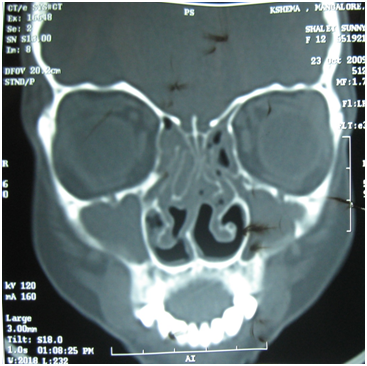

Myers reported cases with intranasal injection of corticosteroids with complete regression of the polyp in few cases, and partial regression in large number of patients. He advocated the use of repeated injections of steroid into the polyp and concluded this method is very useful in patients where surgery need to be avoided.12 Intranasal injections is not a routine practice now; instead steroid preparations are used most commonly as nasal spray or drops, and sometimes systemically. A short course of oral steroid followed by intranasal steroid spray can significantly reduce the nasal polyp, at times complete regression (Figure 4) & (Figure 5). Topical steroids have been investigated extensively. In all patients the addition of simple saline nasal douche for cleaning the nose prior to topical medications is beneficial, as these irrigations have been shown to improve nasal mucocilliary clearance.13

Figure 4 CT scan of a patient with bilateral nasal polyp (before treatment).

Figure 5 CT scan of patient in figure 4, after a short course of oral steroid and follow up intranasal steroid spray.